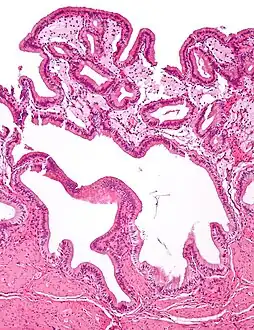

Micrograph of cholesterolosis of the gallbladder Micrograph of cholesterolosis of the gallbladder

Micrograph of cholesterolosis of the gallbladder Micrograph of cholesterolosis of the gallbladder

The name strawberry gallbladder comes from the typically stippled appearance of the mucosal surface on gross examination, which resembles a strawberry. Cholesterolosis results from abnormal deposits of cholesterol esters in macrophages within the lamina propria (foam cells) and in mucosal epithelium. The gallbladder may be affected in a patchy localized form or in a diffuse form. The diffuse form macroscopically appears as a bright red mucosa with yellow mottling (due to lipid), hence the term strawberry gallbladder. It is not tied to cholelithiasis (gallstones) or cholecystitis (inflammation of the gallbladder).[2]